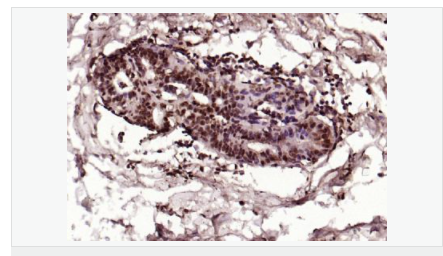

交叉反應(yīng):Human,Mouse,Rat(predicted:Dog,Pig,Rabbit,GuineaPig) 推薦應(yīng)用:IHC-P,IHC-F,ICC,IF,Flow-Cyt,ELISA

| 產(chǎn)品應(yīng)用 | ELISA=1:5000-10000 IHC-P=1:100-500 IHC-F=1:100-500 Flow-Cyt=1μg/Test ICC=1:100 IF=1:100-500 (石蠟切片需做抗原修復(fù)) not yet tested in other applications. optimal dilutions/concentrations should be determined by the end user.  |